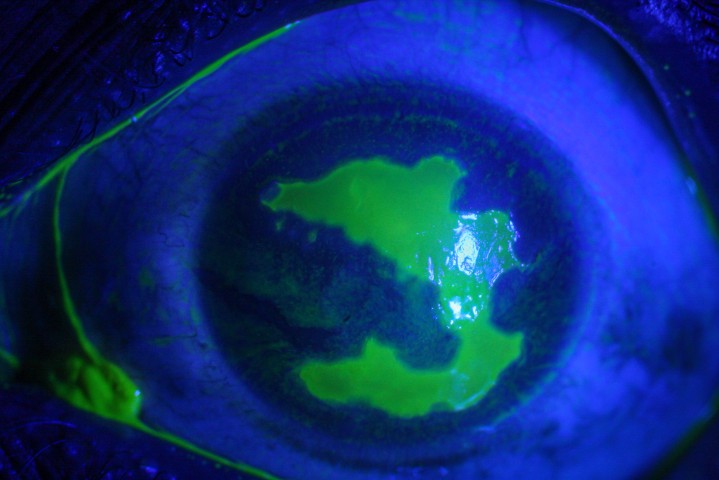

Acanthamoeba keratitis, almost exclusively seen in CL wearers, carries a much higher visual morbidity than bacterial CLMK and thus warrants special mention. The protozoan Acanthamoeba is ubiquitous in the environment, distributed in air, soil and water sources. The ability to transform into chemically resistant cysts in response to challenging environments allows Acanthamoeba to survive in chlorinated swimming pools and most CL multipurpose cleaning solutions4. Local data in Auckland show rising cases of Acanthamoeba keratitis peaking in the summer months from February to April5. Whether this suggests a climactic response in virulence or a higher rate of casual CL wear with high-risk behaviours has yet to be elucidated. Diagnostic delay is common, as the classic ring infiltrate with radial perineural infiltrates is only present in the late stages, whilst the early presentation of punctate epithelial erosion is commonly misdiagnosed as contact lens overwear (Fig 1). Other features overlapping with bacterial CLMK include stromal infiltrate (40%), anterior chamber reaction (29%) and epithelial defect (76%)5. Therefore, a high index of suspicion is required in all CLMK and begins with documentation of Acanthamoeba specific risk factors including hot-tub use, swimming and use of tank water supply5. Empirical therapy with antibiotics for bacterial CLMK usually leads to an initial improvement of symptoms (depleting the cornea of Acanthamoeba’s main nutritive source, bacteria), followed by a relapse once treatment is ceased.